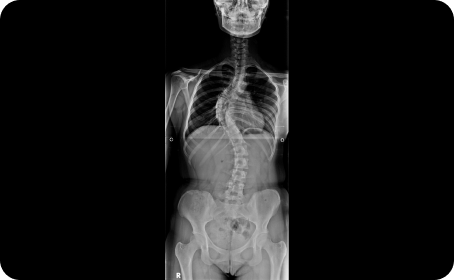

척추의 부정렬이 있는지 확인하는

체형검사, 엑스레이 검사

척추교정치료 병행

척추측만증, 굽은등, 편평등, 거북목 등 틀어진 척추정렬을 추나와 도수로 교정하여 소화기로 가는 자유신경을 회복합니다.